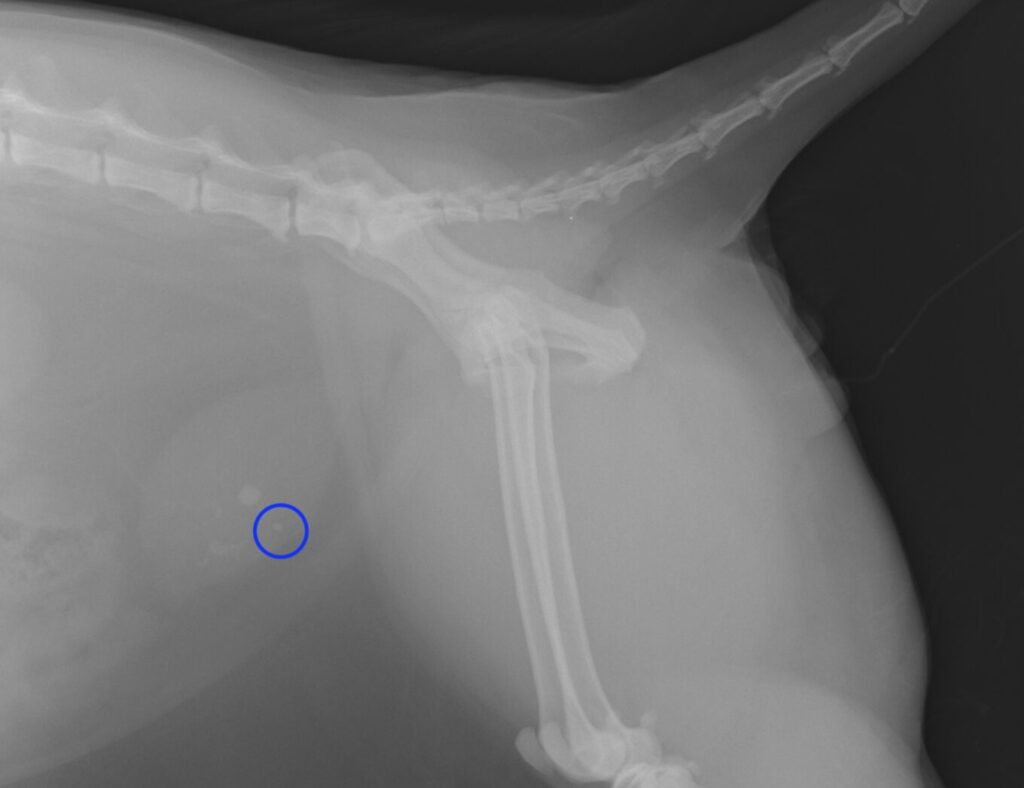

*青枠;尿道に詰まっている小さな石です。